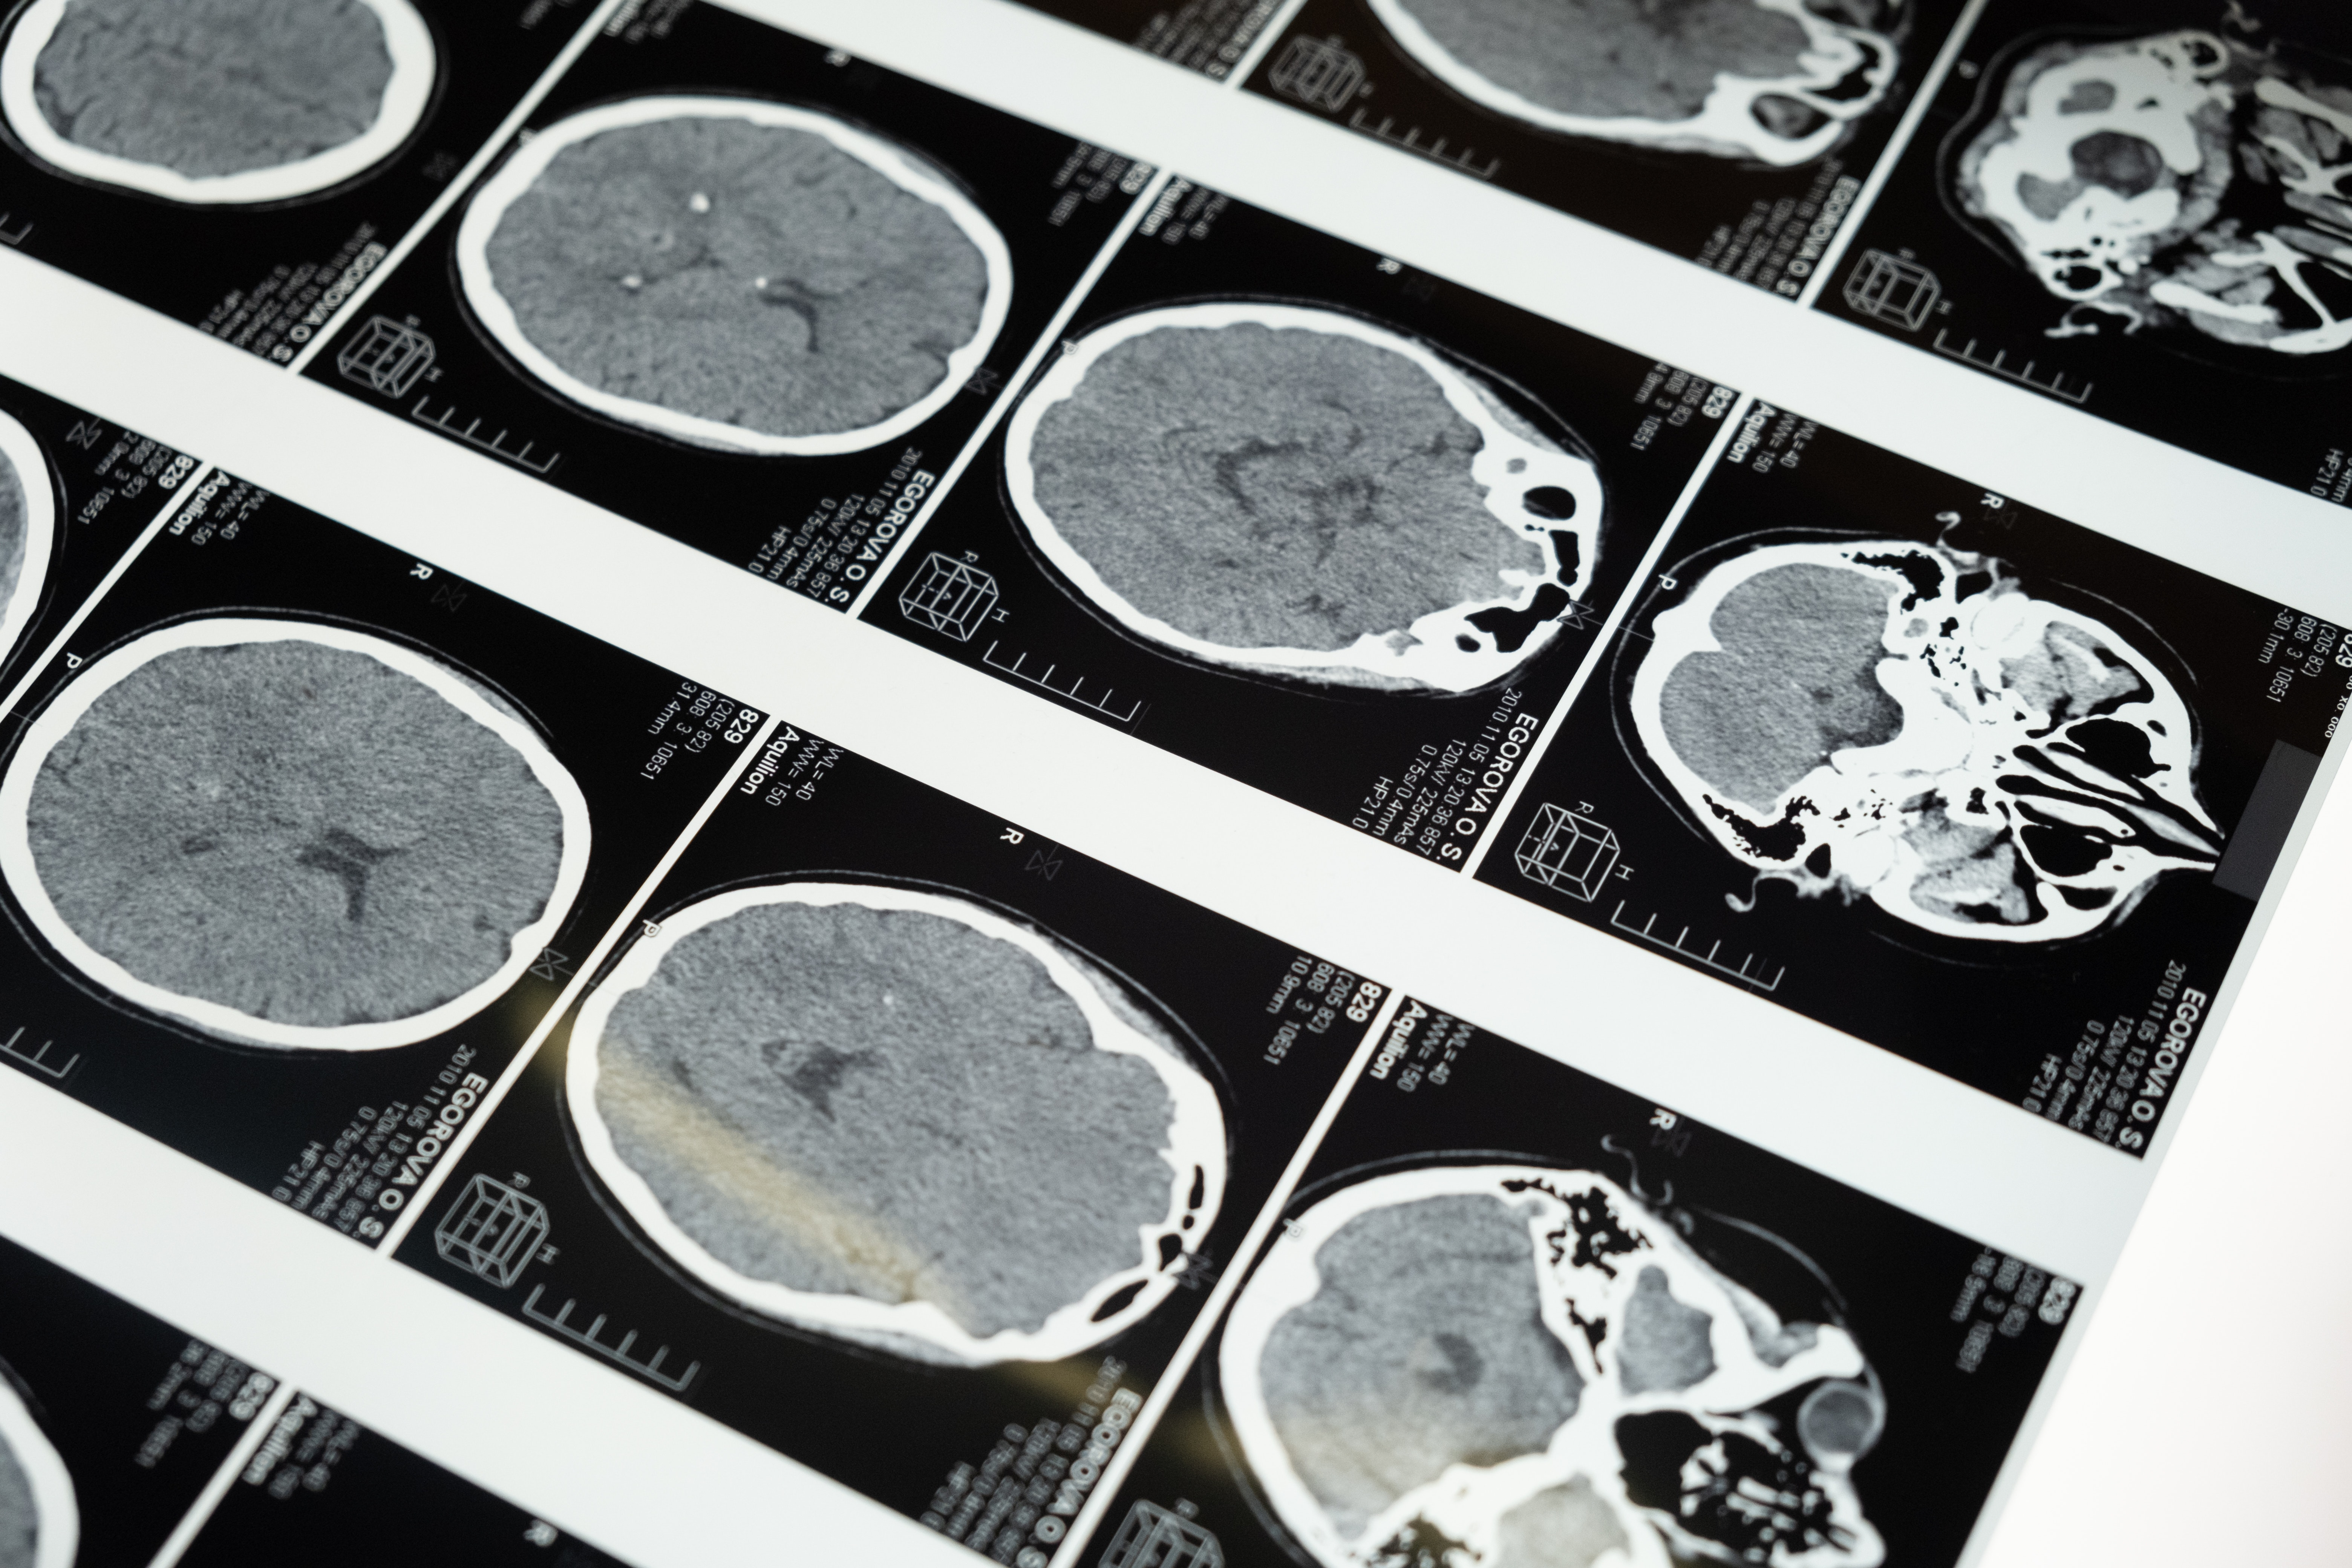

Neki dijelovi mozga mogu doseći temperaturu do 40 °C, pokazuje nova studija, iako to varira ovisno o spolu, dobi i ostalim čimbenicima. Za usporedbu, prosječna oralna temperatura u ljudskom tijelu obično je niža od 37 °C.

Tim je koristio tehniku nazvanu spektroskopija magnetske rezonancije (MRS), koja uključuje mjerenje kemijskih uzoraka kroz magnetska polja. Te su informacije kombinirali s podacima o cirkadijalnim ritmovima i dobu dana.

Daljnji testovi na 114 ljudi koji su pretrpjeli traumatsku ozljedu mozga pokazali su da je u tim slučajevima temperatura mozga još više varirala, od 32,6 °C do 42,3 °C.